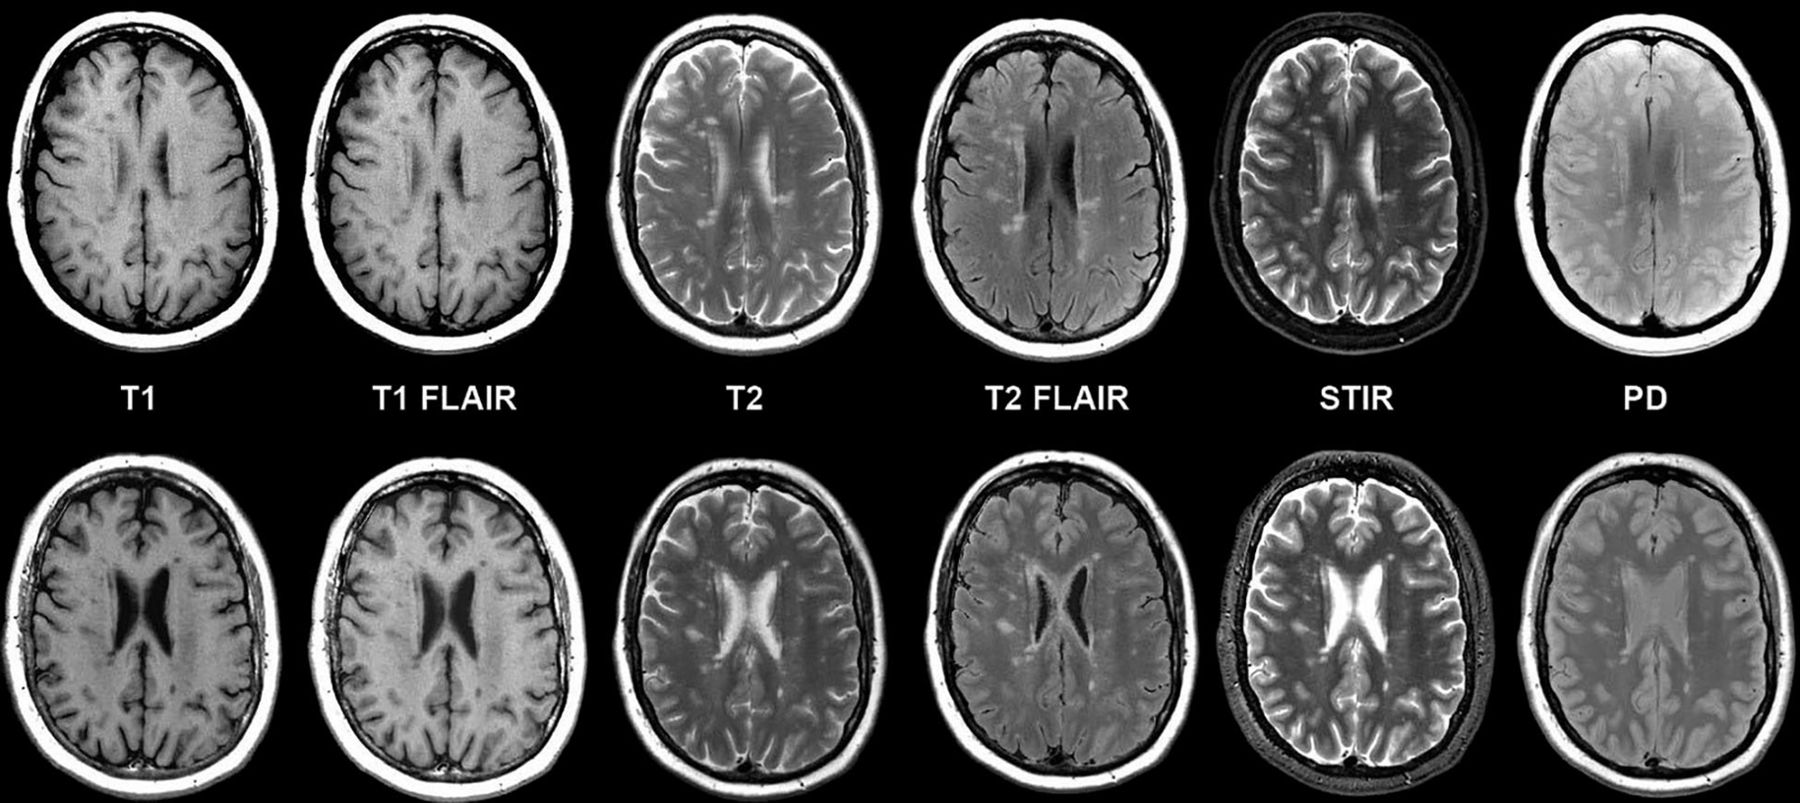

Fazekas grades. T1 t2 Flair. MRI t1 t2. T1 t2 мрт. T1 t2 fleur мрт.

Fazekas grades. T1 t2 Flair. MRI t1 t2. T1 t2 мрт. T1 t2 fleur мрт.